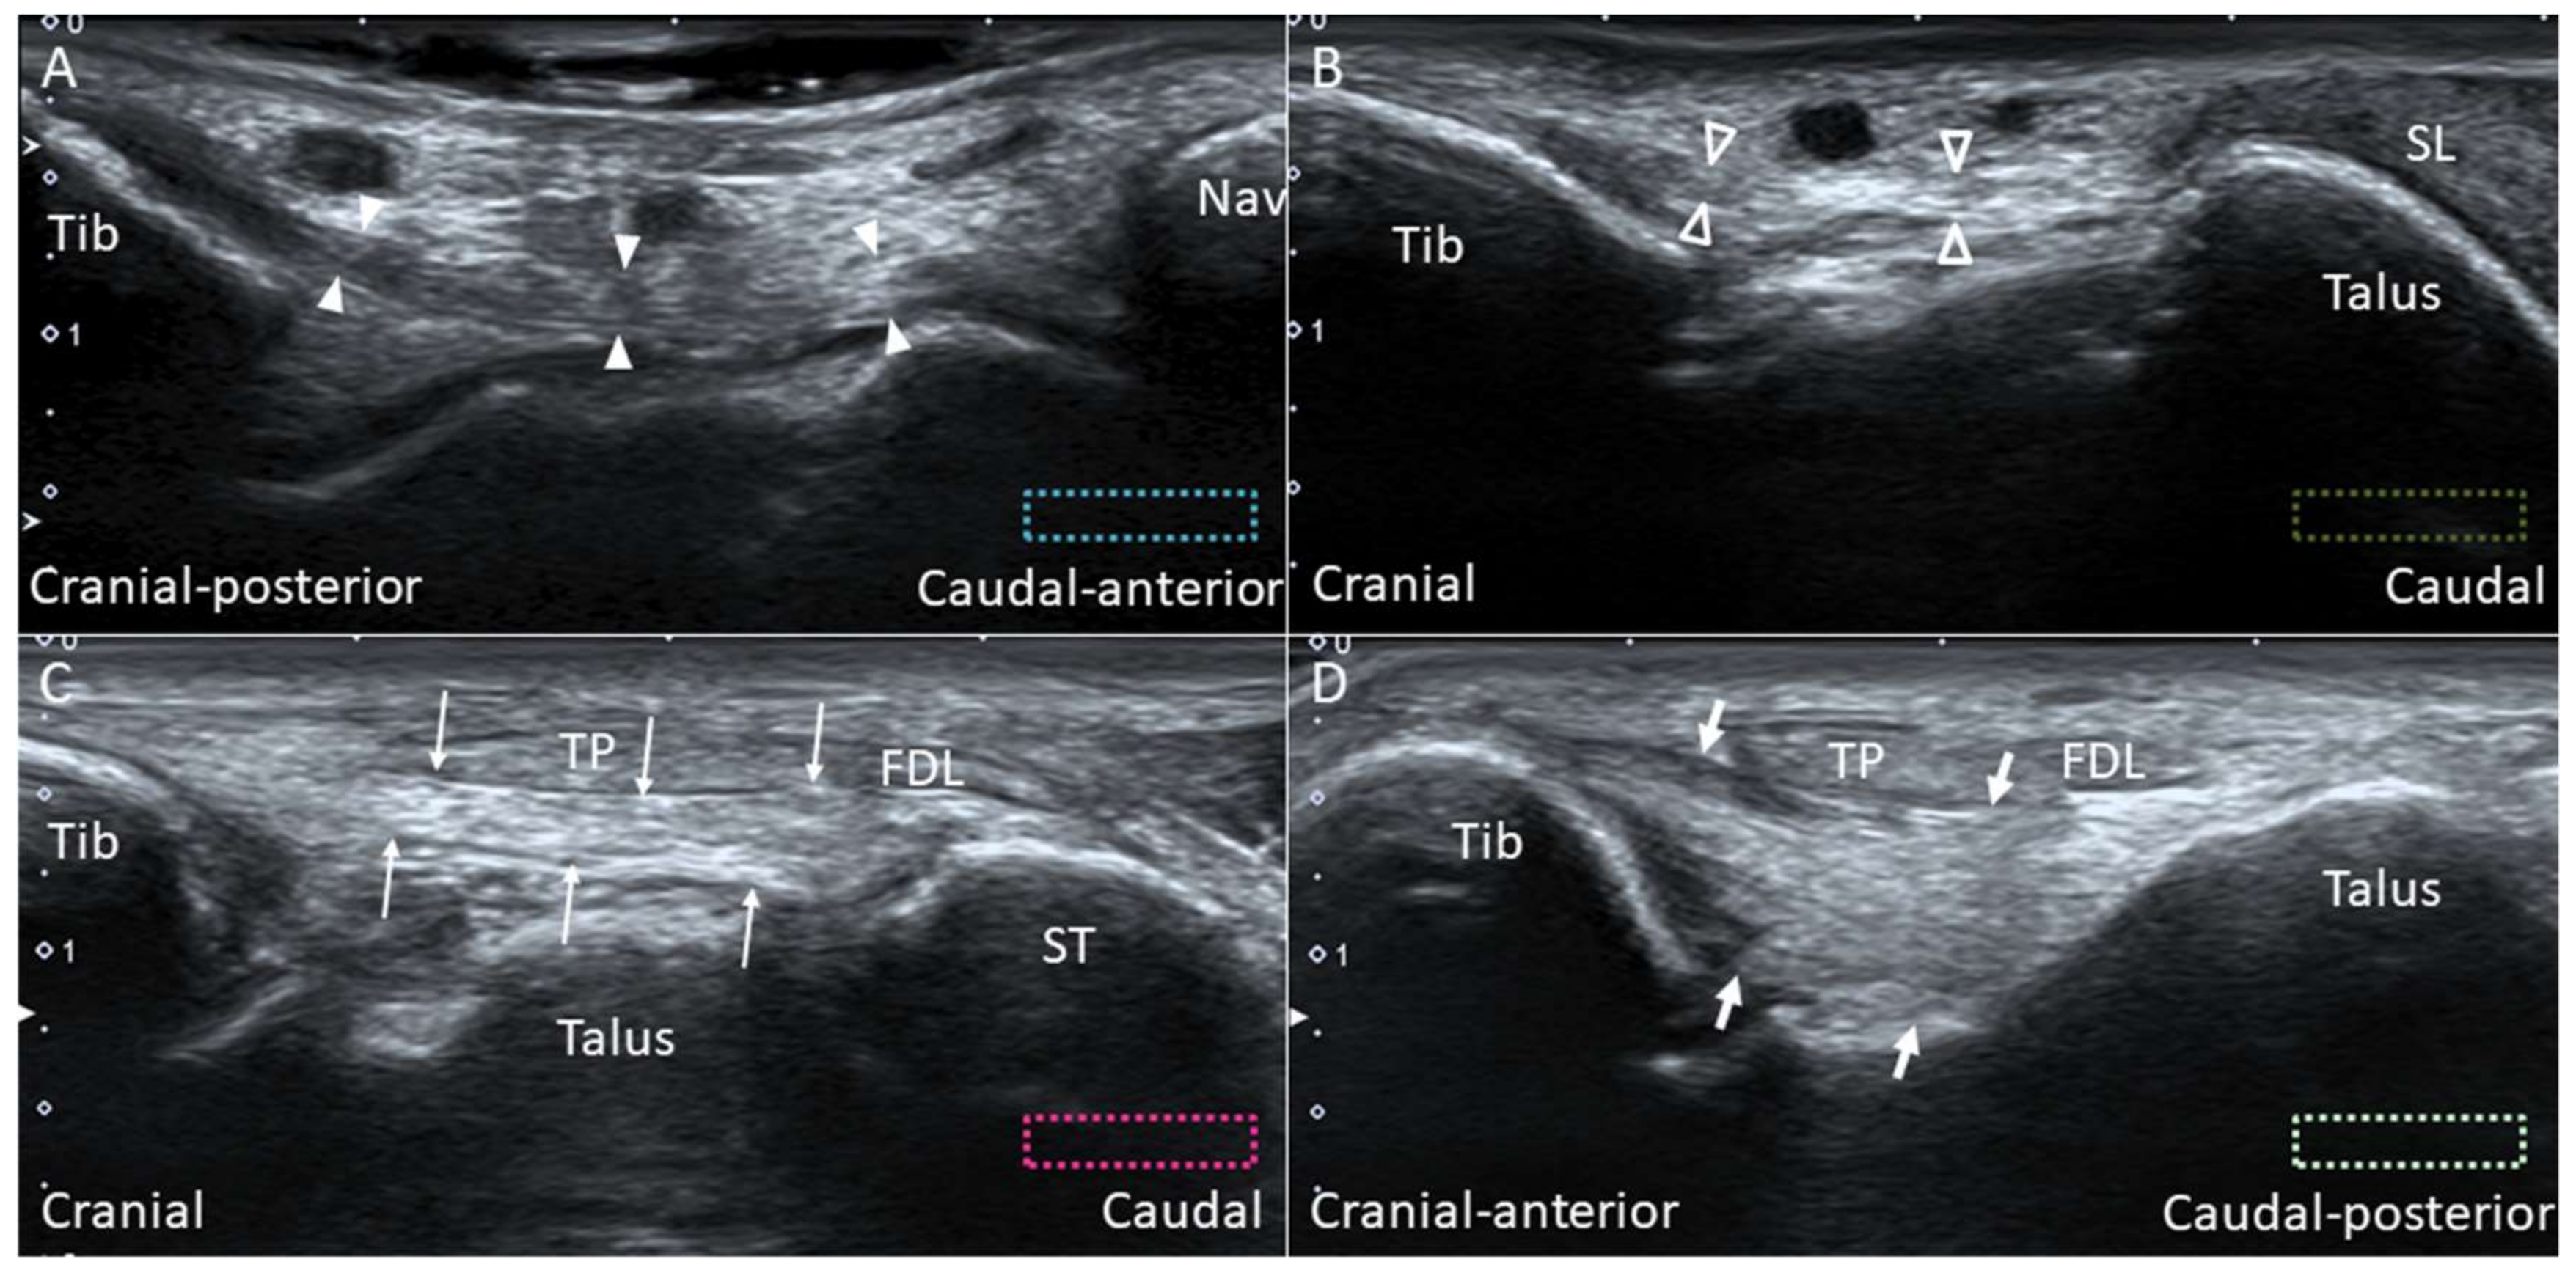

2.7. Deltoid Ligament

2.7.1. Anatomy

2.7.2. Scanning Technique

2.7.3. Clinical Relevance

2.8. Spring Ligament

2.8.1. Anatomy

2.8.2. Scanning Technique

2.8.3. Clinical Relevance